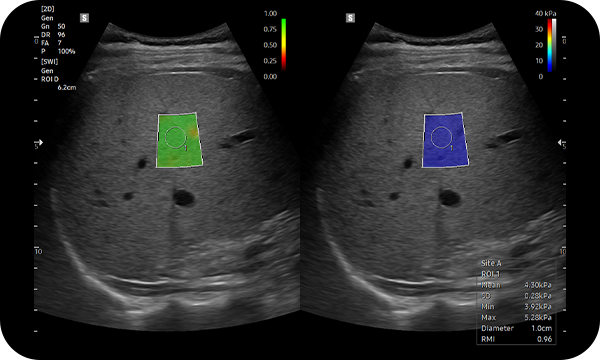

S-Shearwave Imaging™ allows for non-invasive assessment of the stiffness of tissue/lesions liver. The color-coded elastogram, quantitative measurements, dual or single display option, and user-selectable ROI functions are especially useful for the accurate diagnosis liver diseases.